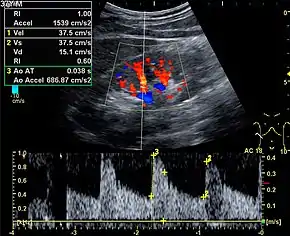

Doppler ultrasonography is widely used in renal ultrasonography. Renal vessels are easily depicted by the color Doppler technique in order to evaluate perfusion. Applying spectral Doppler to the renal artery and selected interlobular arteries, peak systolic velocities, resistive index, and acceleration curves can be estimated (Figure 4) (e.g., peak systolic velocity of the renal artery above 180 cm/s is a predictor of renal artery stenosis of more than 60%, and a resistive index, which is a calculated from peak systolic and end systolic velocity, above 0.70 is indicative of abnormal renovascular resistance).[12]